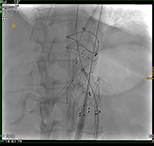

R20-Export_1_vs2 R20-Export_3_vs R20-Export_5_vs_2 R20-Export_7_vs

„Interventionelle Radiologie auf höchstem Niveau“: v.l.n.r: Biopsie einer Metastase eines Tumors der Speiseröhre durch die Wirbelsäule; Implantation einer vierfach verzweigten  Gefäßprothese in der Hauptschlagader zur Ausschaltung eines Aneurysmas; Biopsie eines Tumors in der Verzweigung des Hauptgallenganges mit zwei Biopsienadeln und die Biopsie eines Tumors in der rechten Lunge. (Bilder können durch anklicken vergrößert werden.)